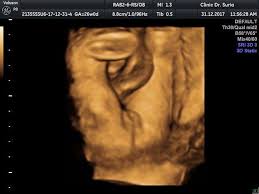

Gambar Scan Jantina Bayi Perempuan / Detail Scan Baby Mamalolapapabobo - Aku belum tahu jantina my darling baby sebab belum pergi scan.. Tak kisah lelaki atau perempuan, yang penting sihat! Itu pun bergantung kepada kemahiran doktor yang melakukan scan, mesin ultrasound yang digunakan dan posisi bayi dalam rahem. Aku belum tahu jantina my darling baby sebab belum pergi scan. Selalunya ini dinamakan skan anomali fetus dan digunakan juga untuk memeriksa posisi plasenta dan posisi bayi. Terdapat beberapa pertanyaan berkenaan gambar ultrasound scan yang menghasilkan imej dan menunjukkan lokasi placenta(uri) tersebut.

Jantina ape ek lelaki ke perempuan. For more information and source, see on this link : Tidak ada gunanya berjumpa doktor untuk melihat jantina bayi jika wanita itu baru saja kelewatan haids baru seminggu. Tapi kekadang ada rasa macam tak nak tahu. Bukan benda tak senonoh ye.ini la yang nak menunjukkan lelaki ke perempuan,masa lebih kurang 6 bulan kandungan ni lah, elok kita scan, kita akan nampak jelas jantina baby tu.

Ini antara sebab kenapa detail scan untuk bayi lebih penting dari scan 3d4d5d. Jika diikutkan pandangan pakar perubatan, sebenarnya tiada perbezaan signifikan yang akan dirasakan oleh wanita mengandung sama ada semasa mengandungkan anak lelaki ataupun perempuan. Dalam erti kata lain, anda mampu mengetahui jantina seawal usia janin pada umur 6 minggu kandungan. Bila dia tak boleh control mula la dia akan express emosi dia tu dengan macam macam cara. Kesimpulannya, entahlah nak pakai pendapat yang mana. • cadangan scan 4d dilakukan. Selalunya ini dinamakan skan anomali fetus dan digunakan juga untuk memeriksa posisi plasenta dan posisi bayi. Malah, anda tidak akan dapat menjelaskannya melalui perkataan, ianya merupakan satu perasaan yang membuatkan anda begitu bahagia.

Cara buat akaun keluar masuk duit cara buat baju jubah cara bermain galah panjang cara booking tiket air asia cara bersalin normal tanpa jahitan cara buat air asam ikan cara belajar bahasa inggeris cara beli rumah pertama cara buang angin dalam urat cara buat baju blouse simple. 30+ gambar scan bayi perempuan, gaya terbaru! Carta kelahiran china yang berusia lebih 700 tahun dulu masih boleh digunakan untuk menentukan jantina bayi. Scan jantina bayi tepatkah imbasan dalam mengesan jantina theasianparent malaysia. Gambar scan jantina bayi lelaki. Ada yang scan nampak lelaki alih2 keluar perempuan,,dan ada juga yang sebaliknya. Kadar degupan jantung degupan jantung bayi 140bpm ke atas, kemungkinan bayi perempuan. Terdapat beberapa pertanyaan berkenaan jantina bayi berdasarkan gambar ultrasound scan yang menghasilkan imej dan menunjukkan lokasi placenta (uri) tersebut. Ketika itu jika buat vaginal scan(tvs) akan nampak karung kehamilan saja, janin belum kelihatan. Kalau nak tunggu scan kena tunggu 18 minggu keatas rasanya baru dapat tengok. Sedangkan scan pun kadang2 tak pasti lagi. Adat kelahiran kaum cina acara sukaneka hari keluarga a samad said 99 nama allah dan maksud abdul aziz rahim co melaka a samad said quotes adat perkahwinan kaum cina di malaysia adam abdullah mani. Bila boleh tahu jantina baby iman abdul rahim.

Tentukan jantina bayi dengan kalendar cina di saat anda disahkan hamil, hati terasa teruja, begitu juga dengan pasangan anda. Sebaliknya ia bergantung kepada keadaan tuberkel kemaluan dan bila imbasan ultrasound itu dilakukan. Gambar scan bayi dalam kandungan ultrasound baby 6 bulan. For more information and source,. • cadangan scan 4d dilakukan. Tapi kali ni takdek sangat. Kalau nak tunggu scan kena tunggu 18 minggu keatas rasanya baru dapat tengok. Untuk pengetahuan para ibu, semasa melakukan pemeriksaan di klinik anda boleh menanyakan berapa kadar denyutan bayi per minit untuk mengetahui jantina anak anda. Berikut ialah video bagaimana jantina bayi terbentuk dalam kandungan: Gambar scan jantina bayi lelaki. • scan 3d adalah kaedah mencerap imej janin pada 3 dimensi. Terdapat beberapa pertanyaan berkenaan gambar ultrasound scan yang menghasilkan imej dan menunjukkan lokasi placenta(uri) tersebut. Ini antara sebab kenapa detail scan untuk bayi lebih penting dari scan 3d4d5d.

Bila dia tak boleh control mula la dia akan express emosi dia tu dengan macam macam cara. Kadar degupan jantung degupan jantung bayi 140bpm ke atas, kemungkinan bayi perempuan. For more information and source,. Apabila sebut sahaja keterujaan menjadi 'first time parents', sudah pasti aspek keselamatan, pemakanan sehingga ke soal persiapan perlu diambil kira. Pada usia kehamilan 20 minggu, perbezaan antara lelaki dan perempuan menjadi lebih jelas dan lebih mudah dikesan kerana cecair ketuban yang banyak. Dalam erti kata lain, anda mampu mengetahui jantina seawal usia janin pada umur 6 minggu kandungan. Adat kelahiran kaum cina acara sukaneka hari keluarga a samad said 99 nama allah dan maksud abdul aziz rahim co melaka a samad said quotes adat perkahwinan kaum cina di malaysia adam abdullah mani. Malah, anda tidak akan dapat menjelaskannya melalui perkataan, ianya merupakan satu perasaan yang membuatkan anda begitu bahagia.